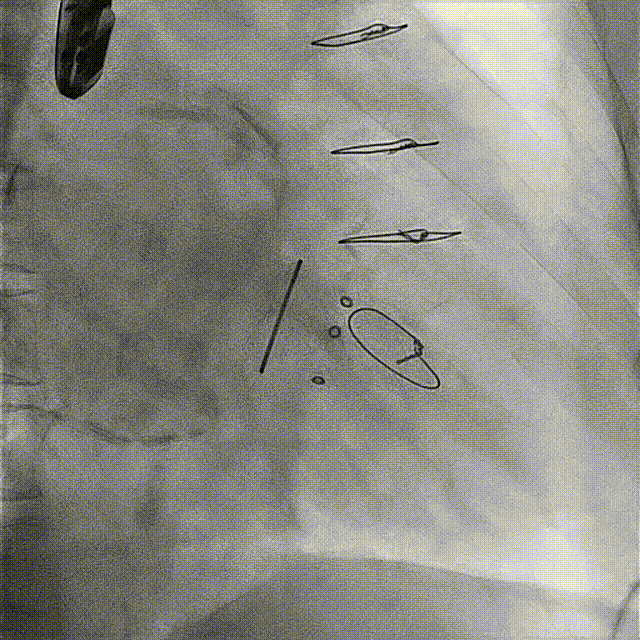

患者手术过程顺利,穿刺右侧股动脉作为TAVR路径,右侧股静脉作为TMVR路径。通过食道超声指引房间隔穿刺,在卵圆窝偏下后方位置顺利进入左房,留置钢丝后全身肝素化;通过右侧股动脉植入20F GORE鞘,按照常规TAVR流程,在主动脉瓣成功进行人工主动脉植入,测定术后压差为0 mmHg。然后通过左房留置钢丝交换可调弯鞘,帮助顺利跨瓣,再次将鞘交换为14 F E-sheath后,在二尖瓣生物瓣位置顺利完成瓣中瓣植入,术后即刻二尖瓣平均跨瓣压差降至4 mmHg。双瓣置换手术成功完成。